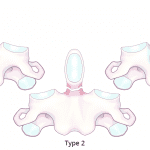

- Acute obliquely oriented fracture through the base of the odontoid (type II) with posterior displacement of the dens relative to the body of C2

- Type II odontoid fracture

Acute obliquely oriented fracture through the base of the odontoid (type II) with posterior displacement of the dens relative to the body of C2.